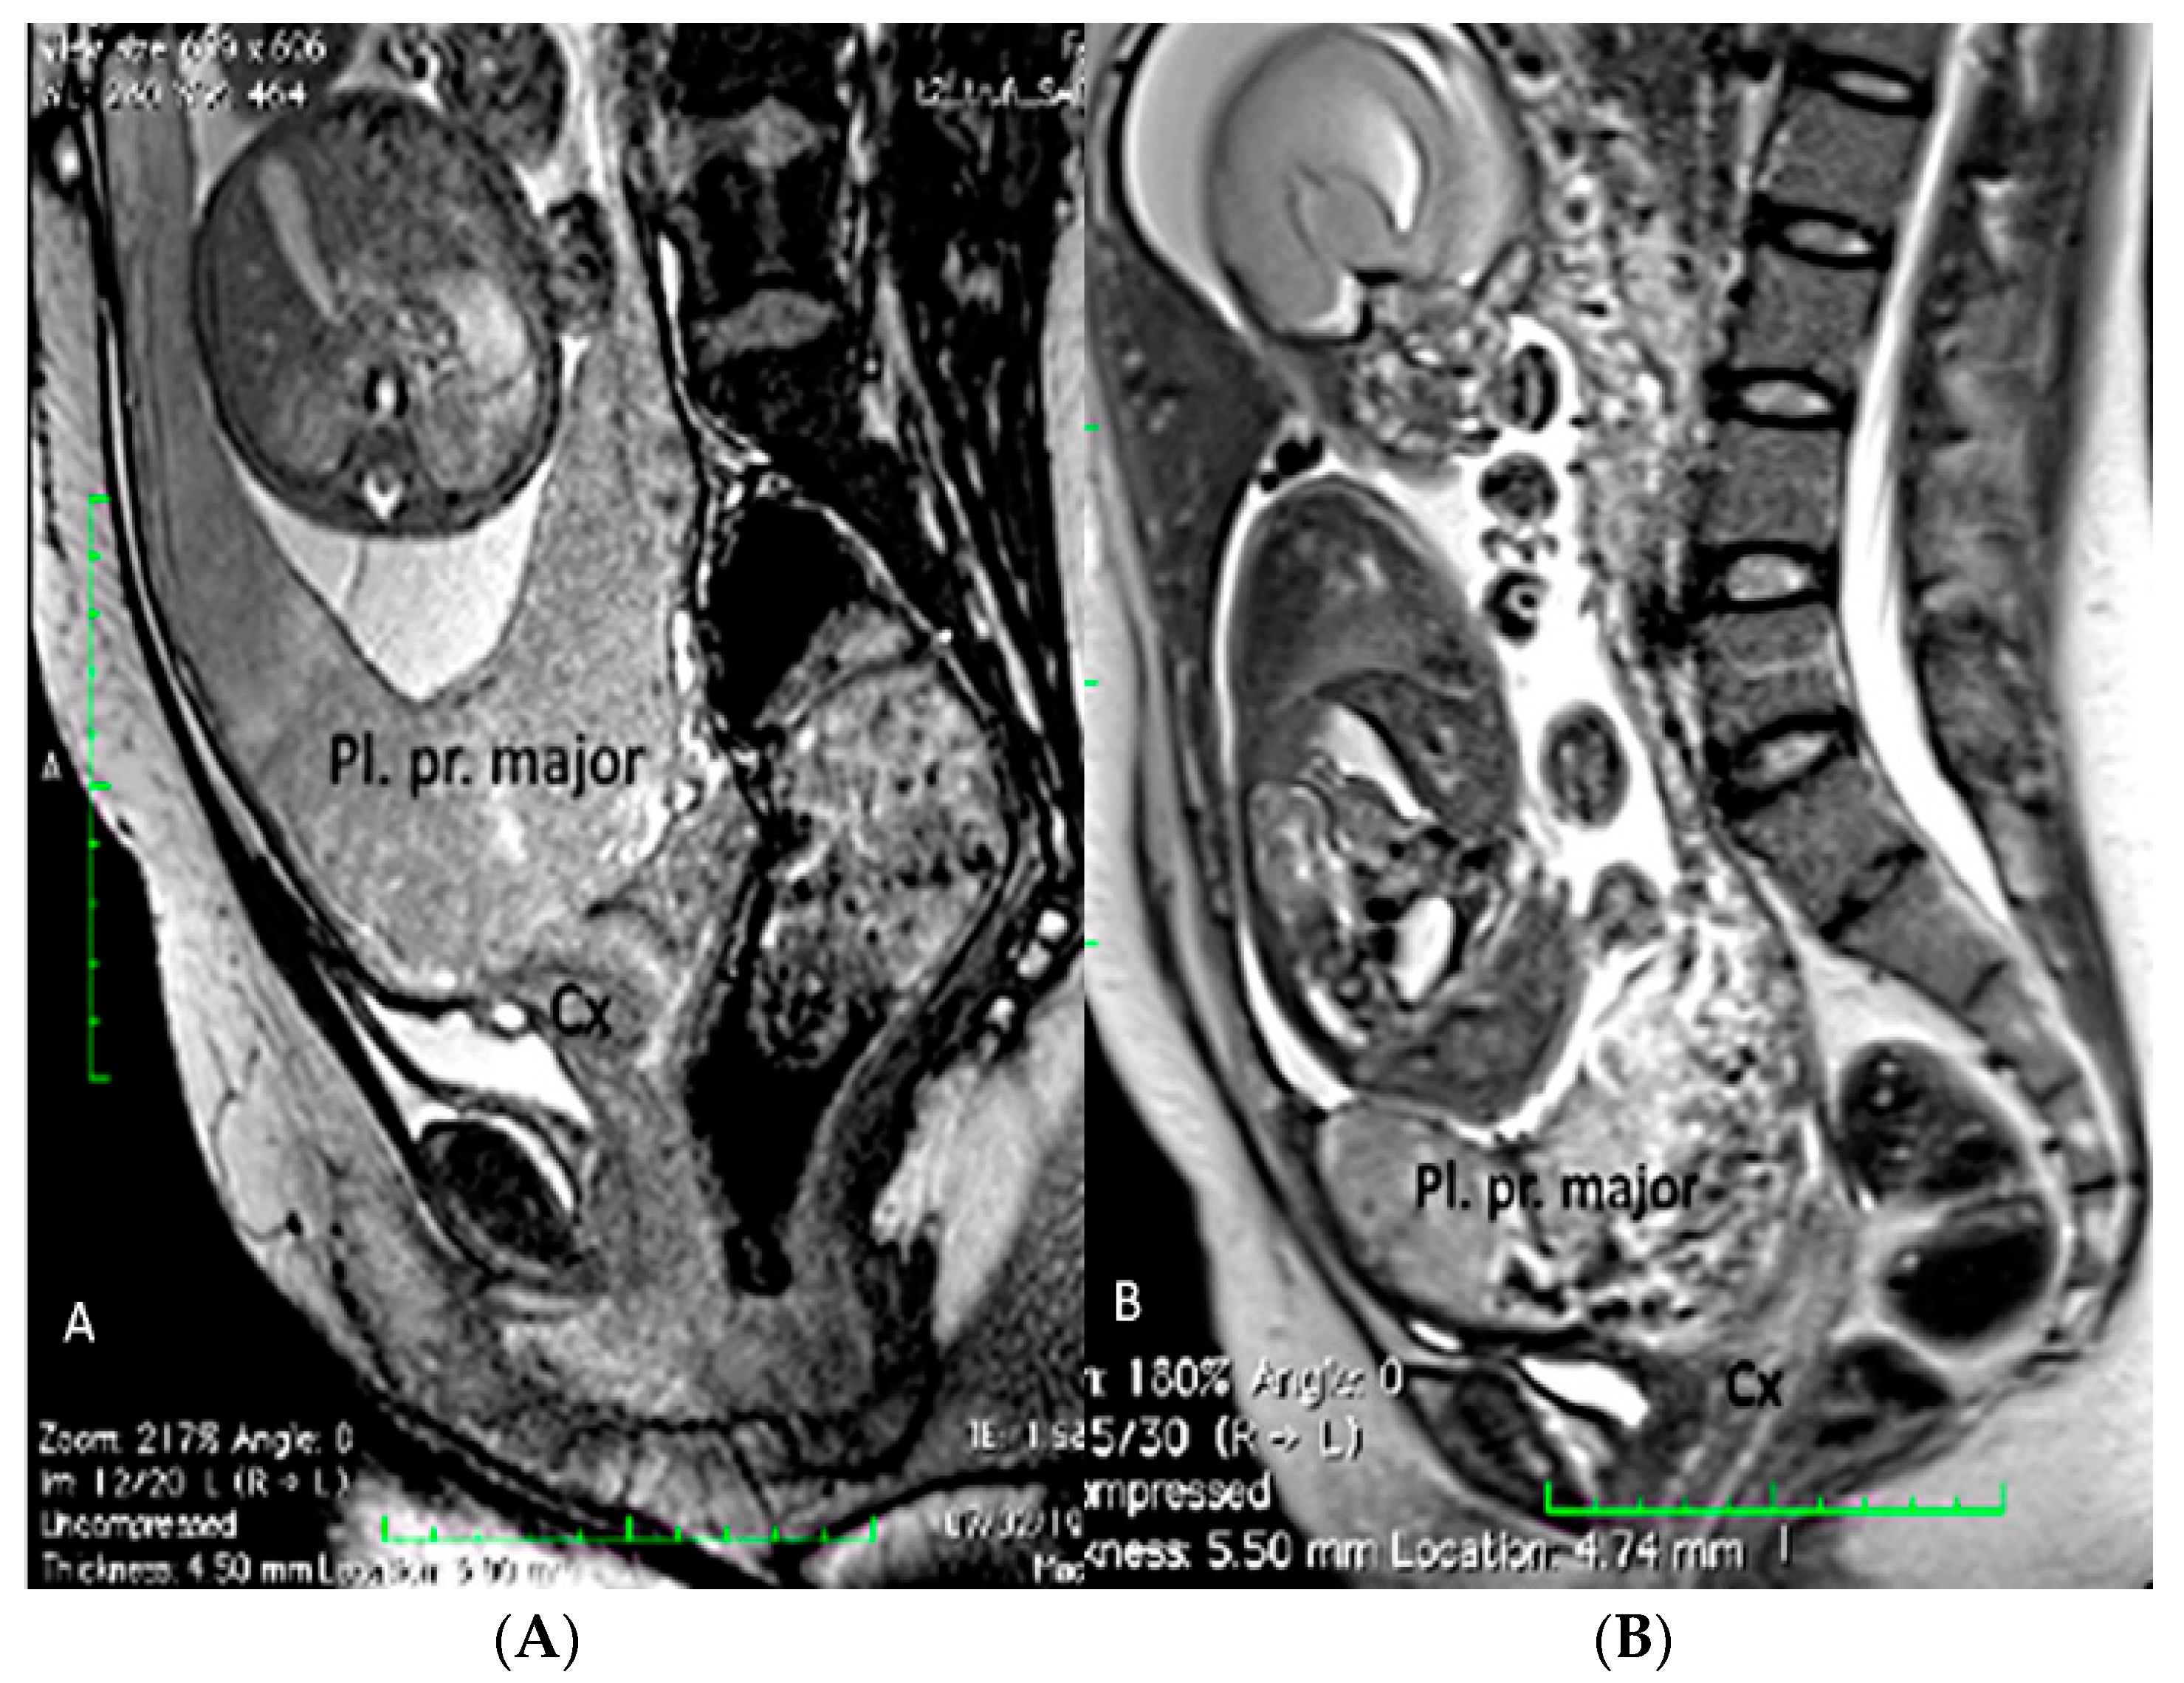

Figure 4.

Fetal MRI (sagittal T2) performed at 30 weeks and 26 week’s gestation in two different fetuses (A,B), demonstrating a placenta praevia major and accretism. (Legend: Pl: placenta; Cx: cervix).